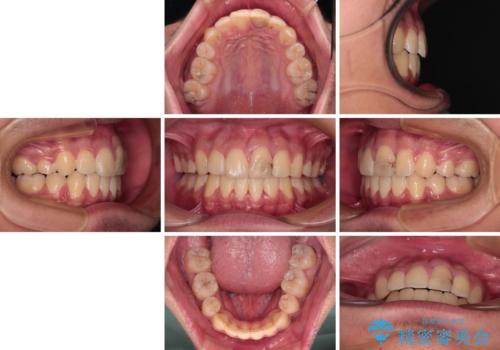

膨らんだ口元 ワイヤー装置での抜歯矯正

- 口元の突出感を気にして来院された患者様です。

上下前歯が著しく前突している状態であったので、上下左右の第1小臼歯4本を抜歯し、ワイヤー装置にて矯正治療を行うこととしました。

小学生の頃に上顎前歯をぶつけ、歯の一部が破損している状態であったので、歯根が歯槽骨と癒着して移動しない可能性がありましたが、無事に治療を終えることができました。